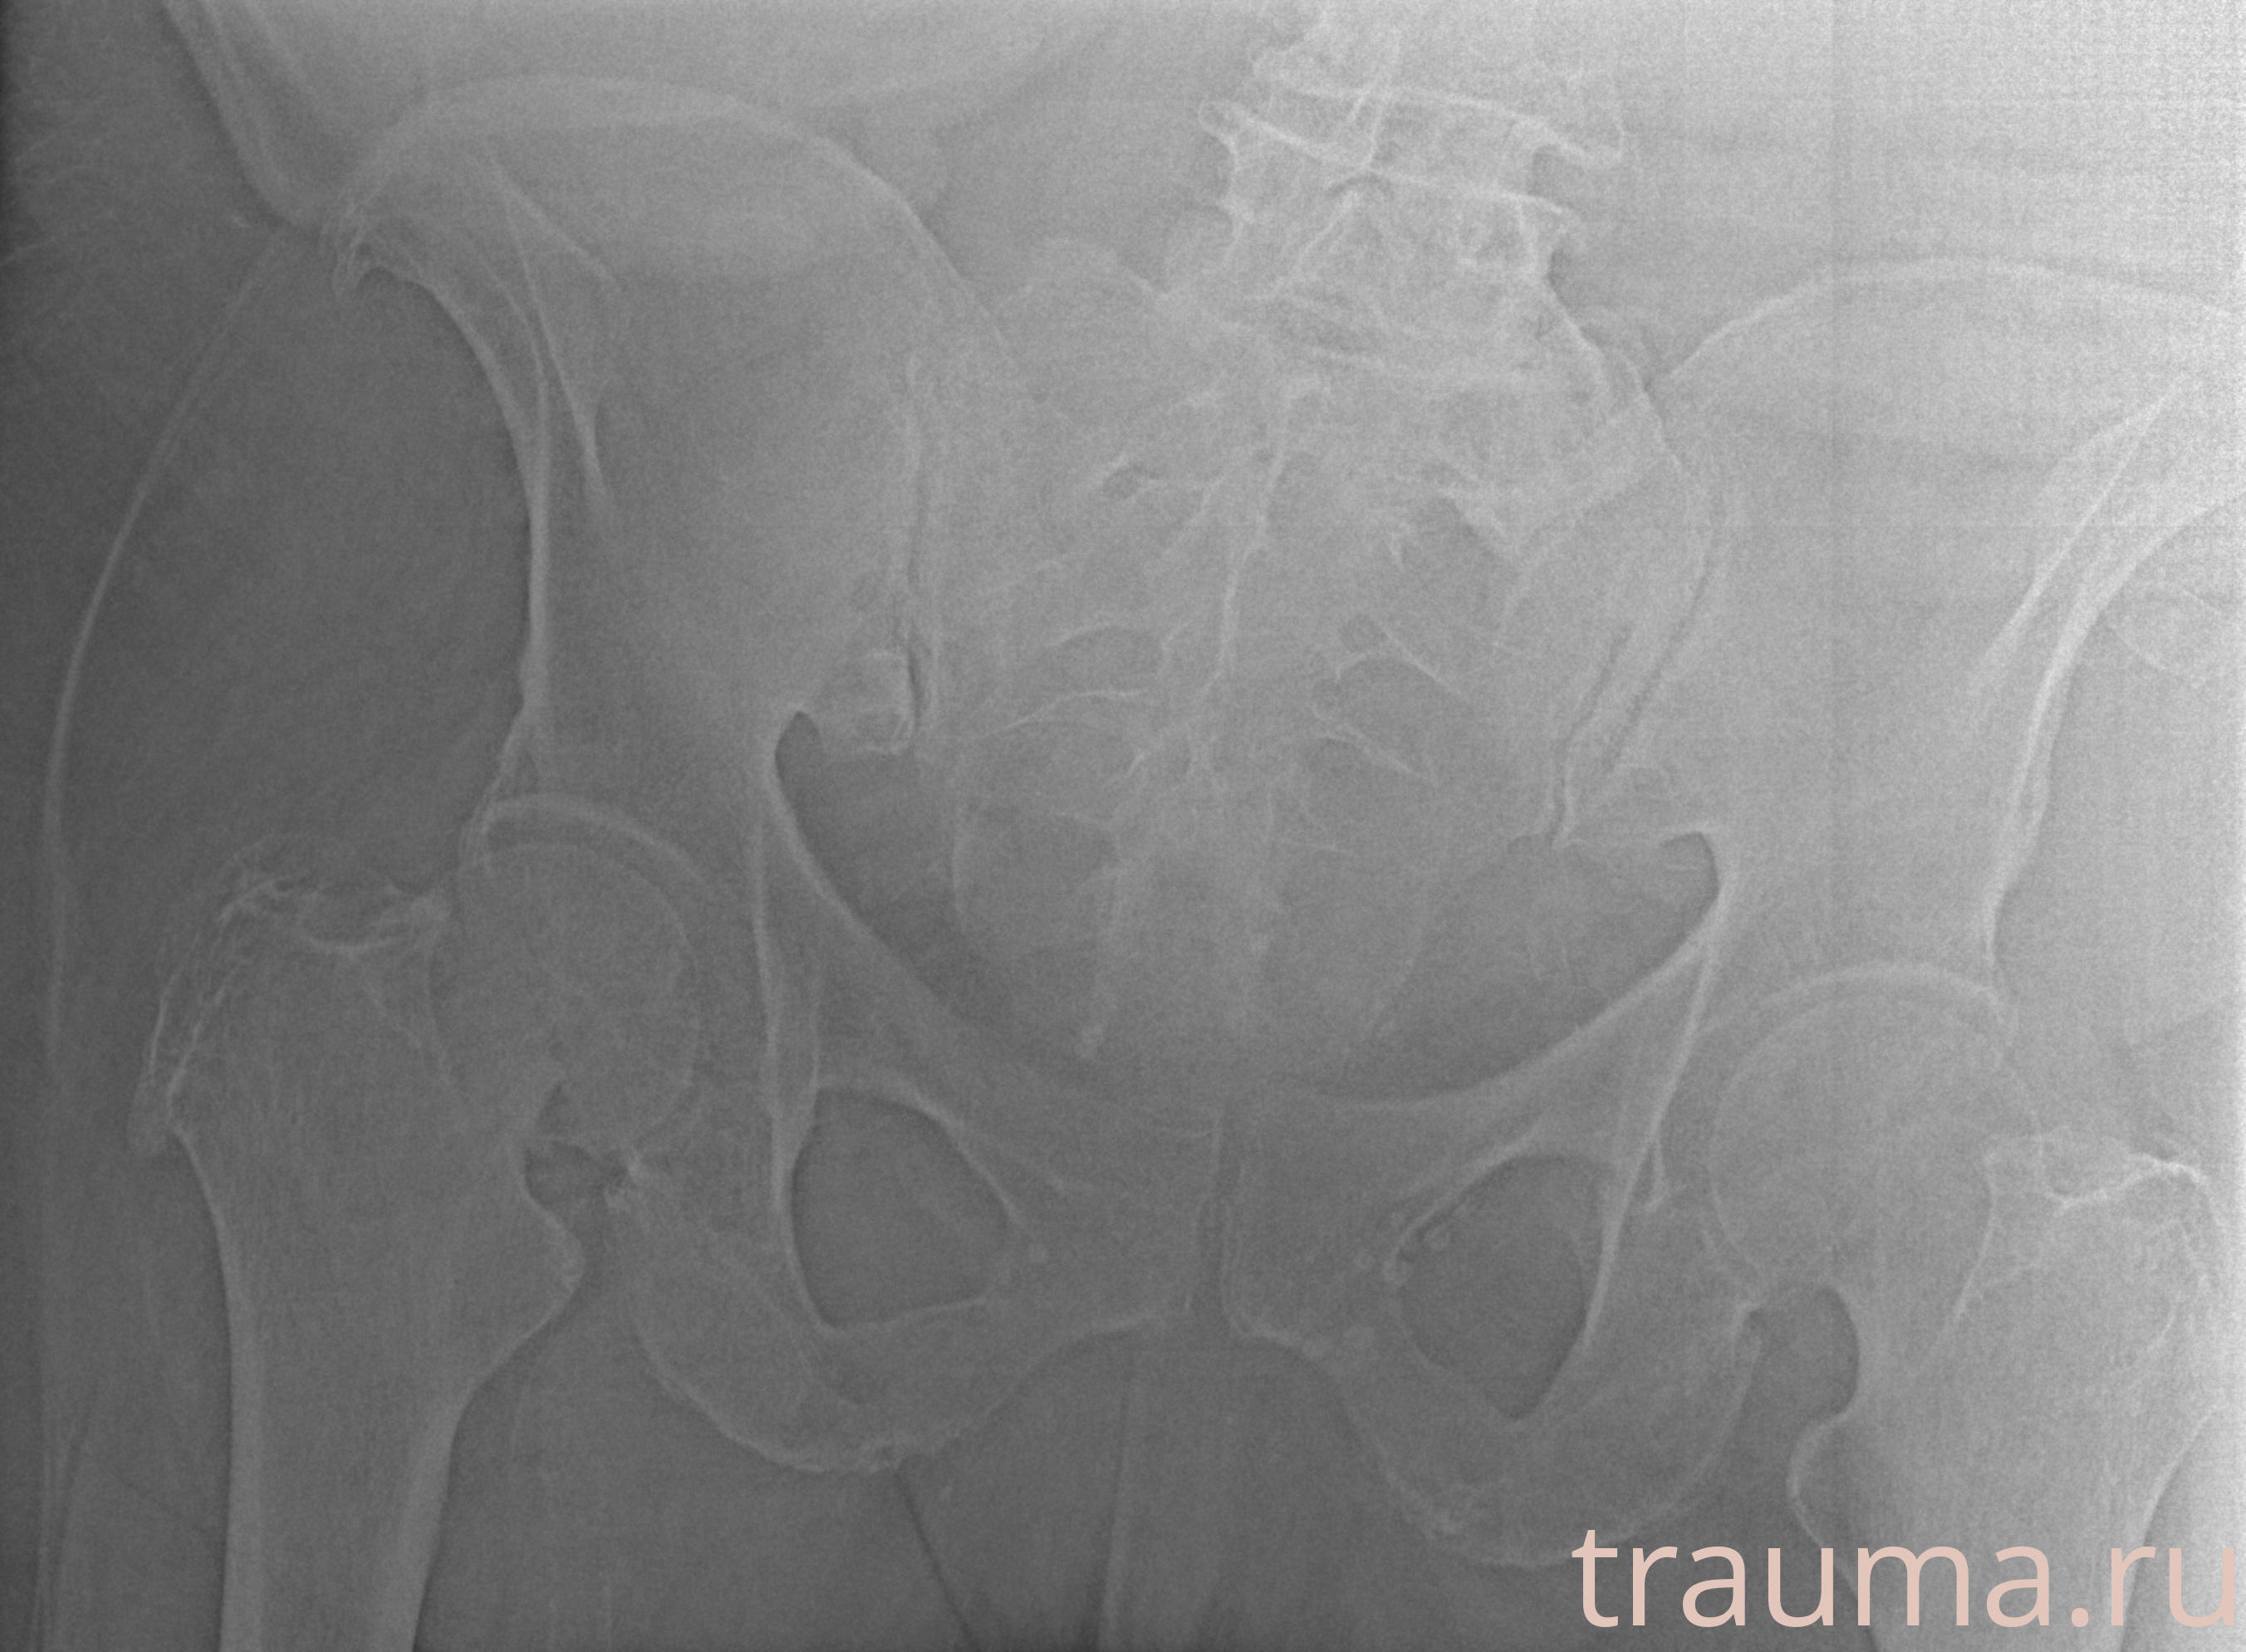

Рентгенограммы

Рентген на дому: по вашему адресу приезжает врач-рентгенолог, травматолог-ортопед с мобильным рентгеновским аппаратом, проводит диагностику травмы или заболевания, делает необходимые рентгенограммы, дает рекомендации по дальнейшему лечению. Получить качественные снимки в домашних условиях возможно благодаря уникальной методике, разработанной МосРентген Центром для института  Склифосовского